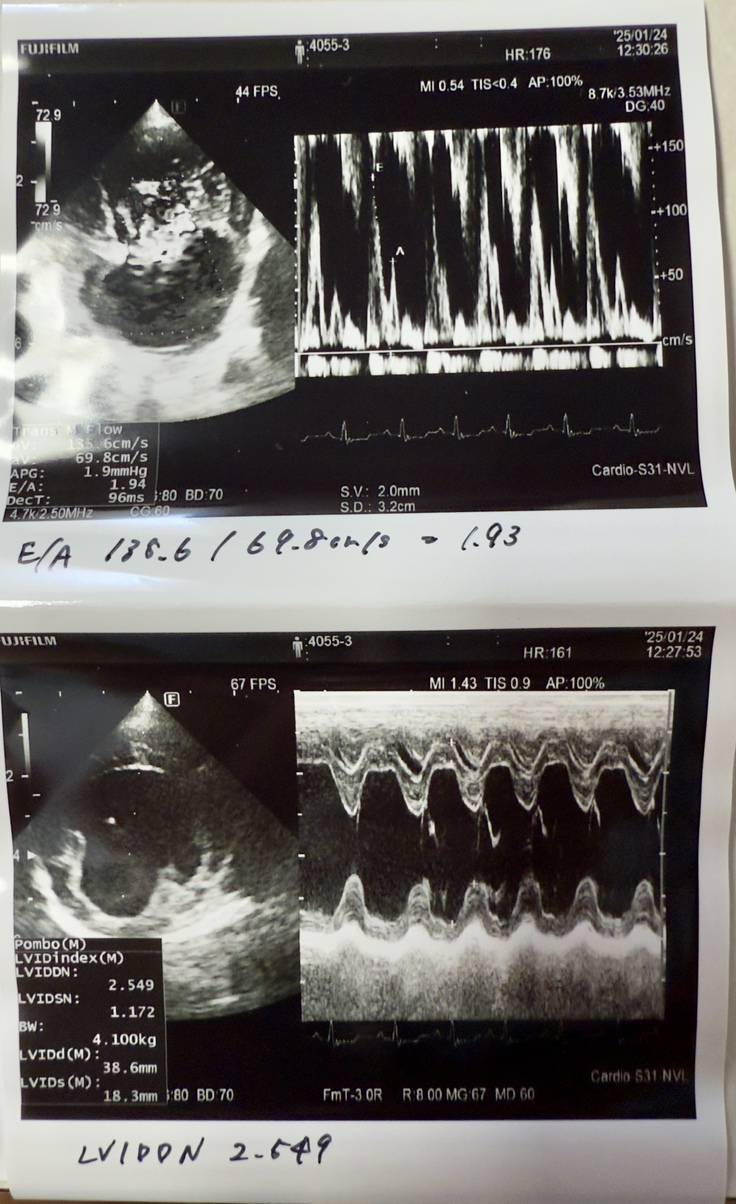

⬇️はシフォンの僧帽弁の逆流を状態を現す心エコーの画像です。(A病院での検査)

分かりにくいですが以下のことが分かります。

※シフォンの心臓は血液の流れを一定方向に保つための僧帽弁がしっかり開閉していないので、血液の逆流や漏れが起きており、心臓に負担がかかり心肥大の状態にあります。